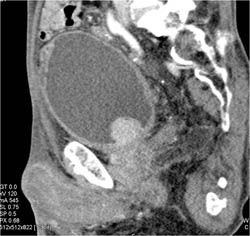

Leak From Bladder